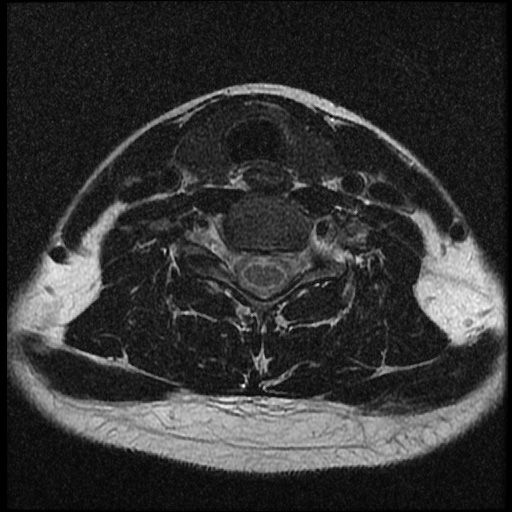

이 MRI 사진은 21년도 사고 당시 찍은 MRI 사진 입니다. 확인 부탁드립니다~

전체 mri를 다 봐여겠지만 보여주신 mri 컷에서는 의미있는 경추 디스크탈출이 보이지 않습니다.